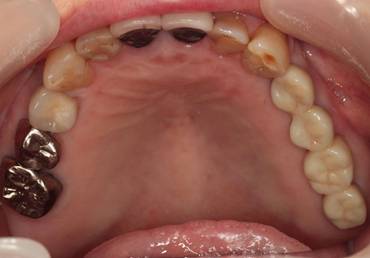

術前。すべての歯が歯周病の末期状態でブリッジ全体がうごいて噛めないとの訴え。右上の犬歯が腫れていました

固定式のブリッジが入っていましたが歯周病で動いています

下顎前歯部には歯石の沈着がみられます